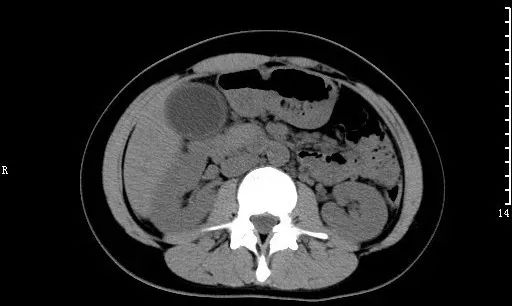

肾结石:CT平扫,右肾见不规则鹿角状高密度影,为铸型结石。